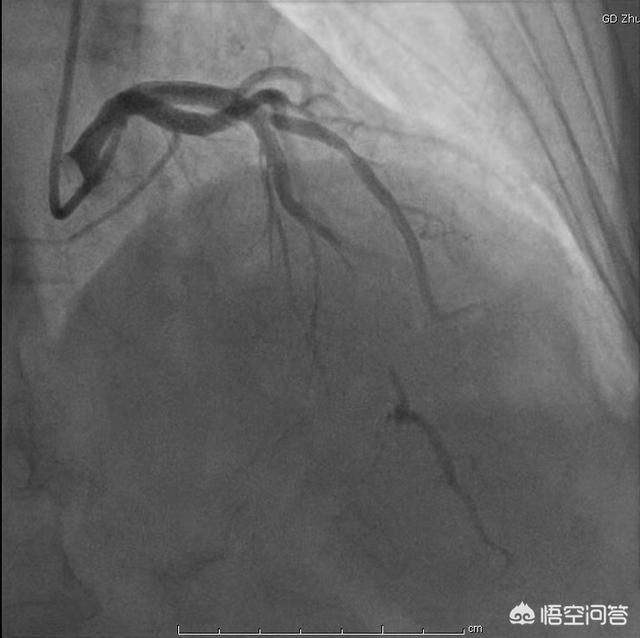

最後に、心電図のST-T変化を写すだけでは、冠動脈性心疾患の有無を判断することはできないことを再認識すべきである。冠動脈疾患のリスクが高い場合は、動的心電図や運動負荷試験で予備的評価を行い、冠動脈疾患が強く疑われる場合は、冠動脈CTAや冠動脈造影検査で最終的な確定診断を行う。

実際、冠状動脈性心臓病は、狭心症、心筋梗塞、不整脈、突然死、無症候性冠状動脈性心臓病(無症候性心筋虚血)など多くの種類に分けられ、狭心症のみが最も一般的な臨床症状である。いわゆる冠状動脈性心疾患は、冠状動脈の血液供給と心筋の酸素需給のアンバランスのために、心筋虚血と低酸素心疾患、50%以上の一般的な冠状動脈の狭窄または心筋虚血は、冠状動脈性心疾患の客観的な証拠を診断することができます。実際、冠動脈の予備能と代償能は非常に強く、例えば、冠動脈狭窄が約50%の患者だけで、日常の一般的な活動、冠動脈の血液供給はまだ保証することができ、激しい活動や心拍数が非常に速い場合にのみ、心筋虚血が発生します。そのため、このような冠動脈狭窄がそれほどひどくない患者は、日常生活ではあまり臨床症状が現れないかもしれないが、運動負荷試験で心筋虚血の証拠を見つけることができる。